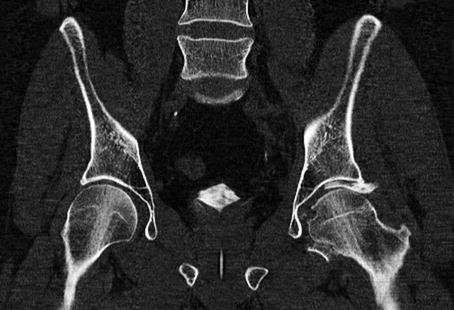

Excessive loading of the proximal femur through the femoral head causes the acetabulum to fracture. In this example, the left-sided unstable acetabular fracture fragments are displaced significantly as the proximal femur intrudes medially into the pelvis